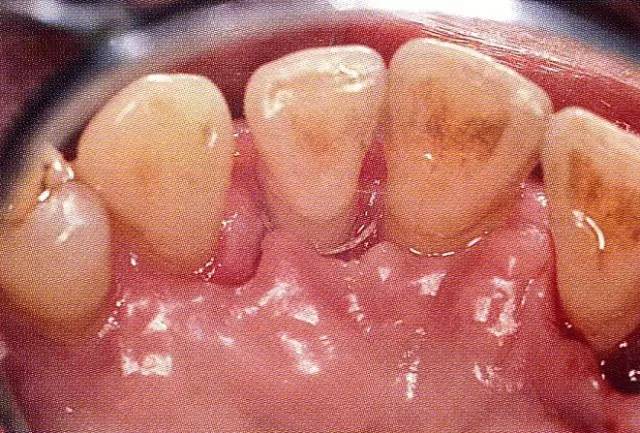

▲圖8-3  進(jìn)行全厚瓣翻瓣,將根表面的沉積物、骨缺損的肉芽組織徹底清除,確認(rèn)牙槽骨形態(tài),可看到從頰側(cè)到遠(yuǎn)中存在垂直性和水平性的骨缺損。

640.webp (10).jpg